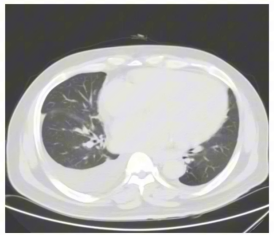

胸部CT:提示双肺间质性病变可能;心脏弥漫性增大;双侧胸腔积液伴双肺部分膨胀不全,右侧为著。

2) 病情发展与处理:利尿治疗后水肿消退不明显,因右侧胸腔积液严重,进行胸腔穿刺引流,引流出2800 ml胸水,胸水性质倾向于漏出液,未发现肿瘤细胞及结核细胞。继续药物治疗后,复查胸部CT提示胸水减少,仍有少量胸腔及心包积液,患者未完全转复,仅心室率得到控制70-90次/分。为明确心衰病因,进行冠脉造影,未发现明显冠脉狭窄,后行心脏核磁检查,发现左室各壁及室间隔增厚,全心运动减低,左心功能不全,左心室各壁心肌增厚,伴有多发斑片状延迟强化。